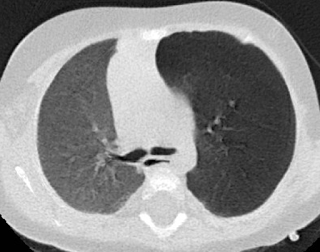

Escanografía